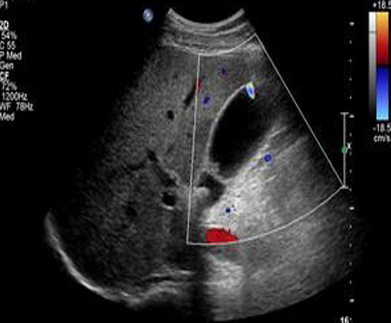

- Image de artefact de scintillement peu obverve

sur echo en Doppler de petit calcul . Resemble une queue de

commet

Les petits calculs vesiculaire peut se

donne de images de artefact brilliant posterieure "

twinkle artefact " . cette artefact peut en voyait

meme sur les calculs renals , et de la vessi |